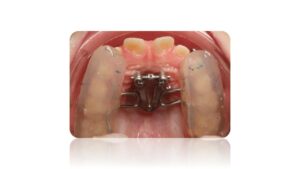

La Classe III Squelettiques

Les classes III squelettiques sont l’expression d’une orientation pathologique du plan occlusal et de la croissance faciale.

L’orthodontie systémique permet d’appréhender cette pathologie par l’analyse des latéralités mandibulaires.

Le traitement qui en découle est donc fonctionnel et stable car il permet non pas seulement une protraction du maxillaire mais une réorientation complète de celui-ci. Cette prise en charge permet de retrouver une proprioception maximale du prémaxillaire dans la mastication, gage de stabilité à long terme.